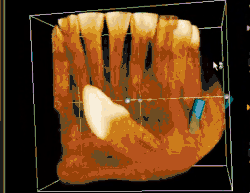

Classifications enable the oral surgeon to determine the difficulty in removal of the impacted tooth. [9] The primary factor determining the difficulty is accessibility, which is determined by adjacent teeth or other structures that impair access or delivery pathway. The majority of classification schemes are based on analysis on a radiograph. The most frequently considered factors are discussed below.

This type of classification is based on the amount of impacted tooth that is covered with the mandibular ramus. It is known as the Pell and Gregory classification, classes 1, 2, and 3.[10]

Relationship of tooth to occlusal plane

The depth of the impacted tooth in relation to the adjacent second molar serves as the foundation for this type of classification. This was also given by Pell and Gregory and is known as the Pell and Gregory A, B, and C classification. Relationship to the occlusal plane A-C classes